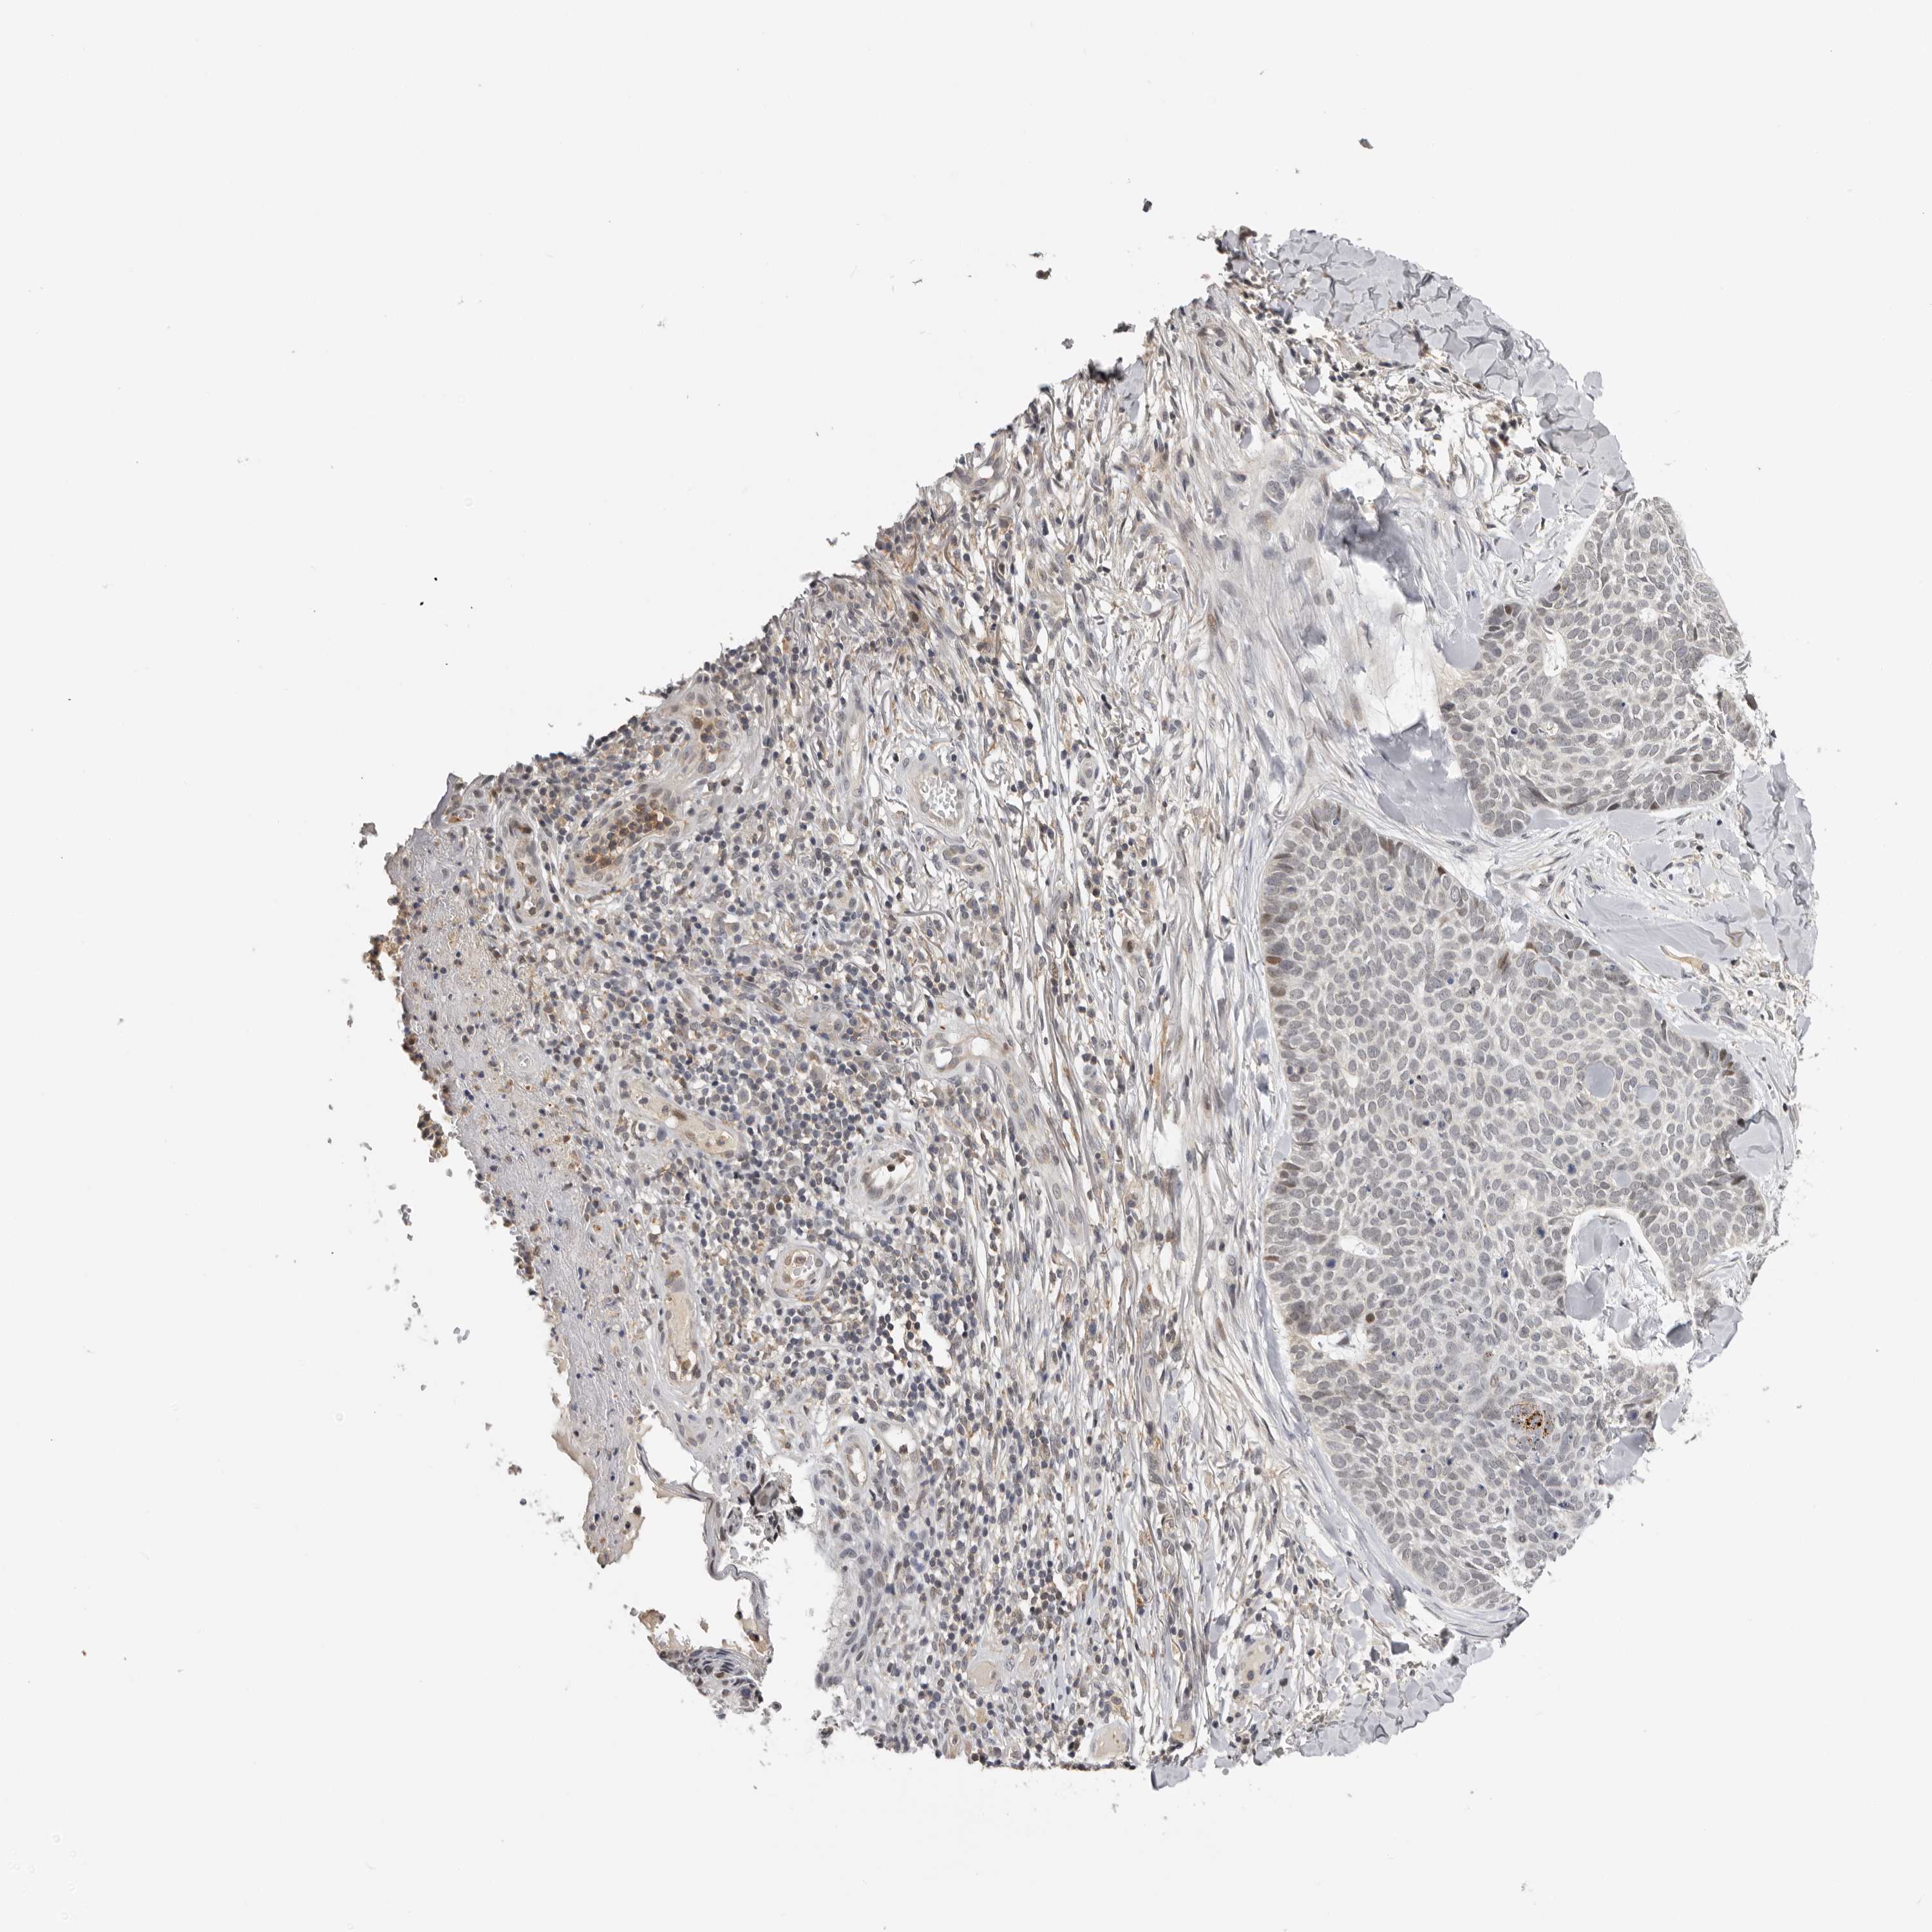

Basal cell and squamous cell cancer

SKIN CANCER - Protein expressioni

A mouse-over function shows sample information and annotation data. Click on an image to view it in a full screen mode. Samples can be filtered based on level of antibody staining by selecting one or several of the following categories: high, medium, low and not detected. The assay and annotation is described here.

Each image is clickable and will lead to virtual microscopy that enables deeper exploration of all samples and also displays staining intensity scores, fraction scores and subcellular localization as well as patient and tissue information for each sample.

Antibody HPA023081

Basal cell carcinoma